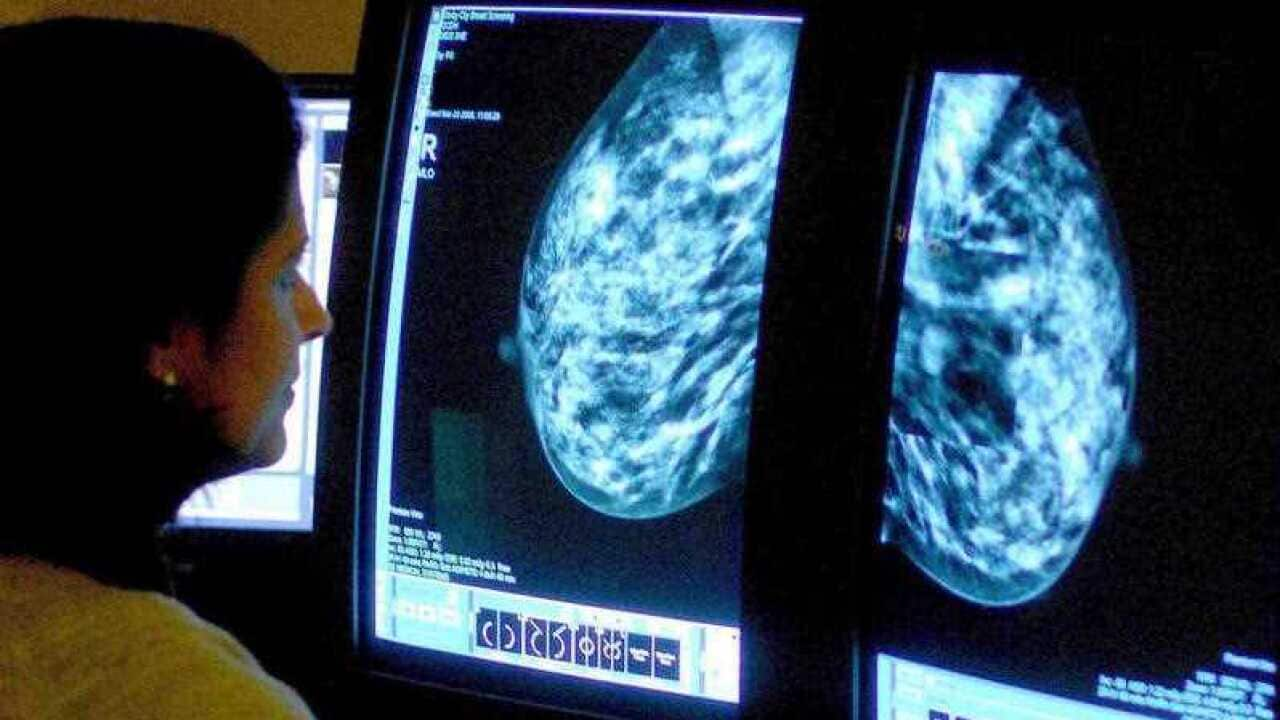

قامت مؤسسة Arabic Welfare بإطلاق برنامج توعوي صحي من خلال نساء رائدات في مجتمعاتهن في ملبورن لكسر حاجز الخوف وتشجيع النساء على الفحص المبكر لسرطان الثدي وأمراض أخرى وذلك لزيادة فرص الشفاء والتعافي.

للحديث عن هذا الموضوع، التقينا بالسيدة سيمار عماد للحديث عن تفاصيل هذا البرنامج الذي استفاد من خدماته حتى الآن أكثر من مئتي امرأة.

المقابلة مرفقة بالصورة أعلاه.